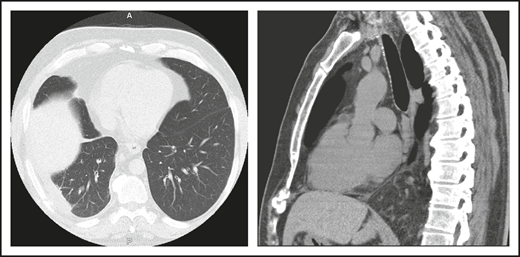

A 46-year-old male contractor who smoked but was previously healthy had acute AIHA. He was treated with prednisone and recovered. This occurred again the following year, and he required blood transfusions. Four years later, AIHA again occurred; he developed a clot in his aorta with thrombosis of his splenic artery, resulting in a splenic infarct. He had a splenectomy and recovered uneventfully. The following year, he developed pneumonia with a large posterior empyema; Streptococcus pneumoniae was cultured (Figure 1). The collection was drained, complicated by a collapsed lung, but he recovered. Six months later, he had a second bacterial pneumonia, and immunoglobulin was measured. These tests showed remarkably low levels of serum immunoglobulins: IgG, 71 mg/dL (normal range, 639-1349); IgA, 6 mg/dL (80-350); and IgM, 15 mg/dL (45-250). He had no protective titers of antibody to any vaccines. Intravenous immunoglobulin replacement was instituted, and the patient experienced no further episodes of either infection or autoimmunity.

(A) The patient in clinical case 1 with several episodes of severe autoimmune hemolytic anemia was only diagnosed with CVID after he had bacterial pneumonia and developed an empyema. (B) Lateral view shows the posterior empyema collection.